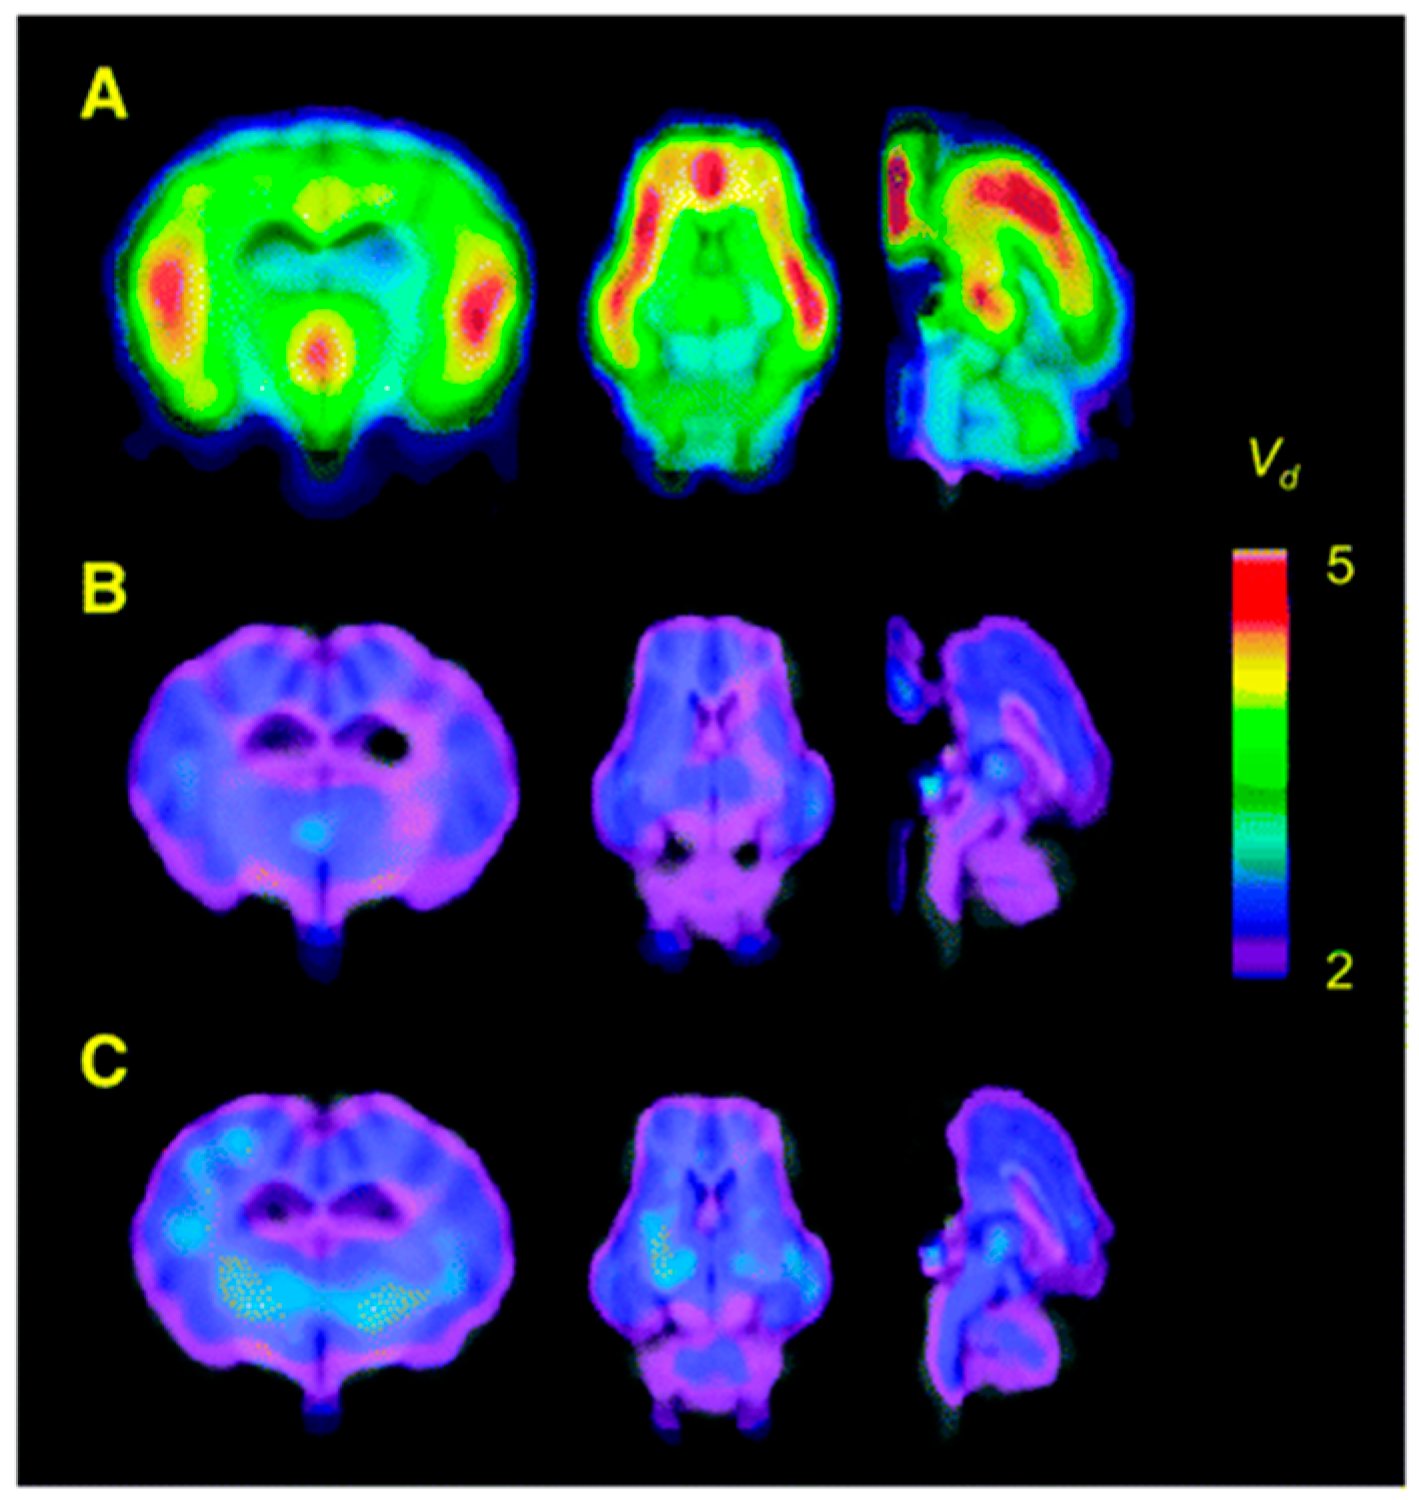

PET studies were performed in pigs to obtain whole-body and dosimetry recordings and for dynamic brain imaging. Interestingly, no radioactive metabolites of 16 were reported in pig plasma and binding of 16 was observed in α2-AR-rich regions where it was displaceable by co-injection of pharmacological doses of yohimbine or selective α2-AR antagonist (Figure 4). Later, 16 was used to image α2-ARs in the human brain (n = 6) using PET [98]. Highest binding of 16 was observed in cortex and hippocampus and the lowest in corpus callosum, which was used as a reference region to estimate the average total distribution (VT) in other brain regions. The radiotracer 16 seems to be a suitable radiotracer to image α2-ARs but has similar issues as of 14, which need to be addressed.

Figure 4. Parametric maps of 16 in living porcine brain. (A) Baseline study using 16 showed regional differences in its distribution. (B) Blocking experiment (yohimbine at 0.07 mg/kg) reduced the scale of distribution volume (Vd) to ~2 mL g−1 in all the α2-AR bound regions. (C) Increased dose of yohimbine (1.6 mg/kg) had no further significant effect in comparison to the low dose (n = 3) Maps are superimposed on the MR image. Adapted from JNM publication by Jacobsen S, Pedersen, K.; Smith, D.F.; Jensen, S.B.; Munk, O.L.; Cumming P [97]. Permission obtained from SNMMI.